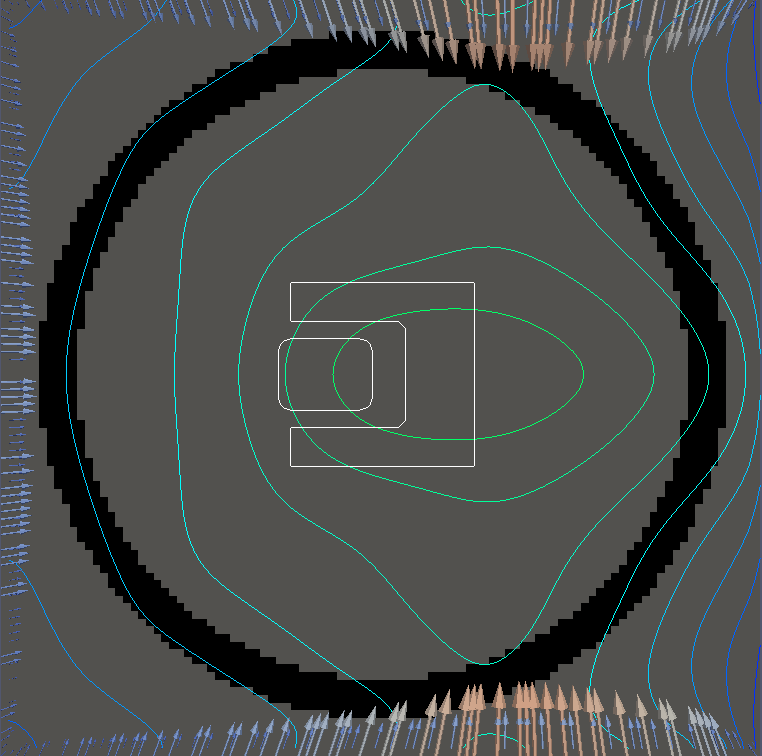

For testing, we use three tumor/risk region regions similar to those in [13]. Specifically, we define the regions in Table 3 and are shown in Figure 1; the void region is shown in black and the tumor and risk regions are traced in white. In the basic target case, seen in Figure 1(a), the tumor region is a box, as is the risk region. The second, intermediate target case, seen in Figure 1(b), involves an L-shaped tumor around a box-shaped risk region. Finally, the complex target case in Figure 1(c) involves a C-shaped tumor around a risk region.

Figure 2 shows the optimal boundary source term for both and The vectors shown on the boundary are the time-integrated values of normalized and then scaled by In Figures 2(a), 2(c), and 2(e) (corresponding to ), the isolines are spaced at intervals of the maximum of the desired dose (here, 5). In the intermediate and tracking cases, we see that relatively low dose levels are attained, primarily due to the high penalty to any dose deposited in the risk region. In Figures 2(b), 2(d), and 2(f)(corresponding to ), the isolines are spaced at intervals of of cells killed. Here a high proportion of the tumor cells are killed (in each case ) while in the Intermediate and Basic cases, the tumor has at least survival; in the Complex case, the risk region has survival.